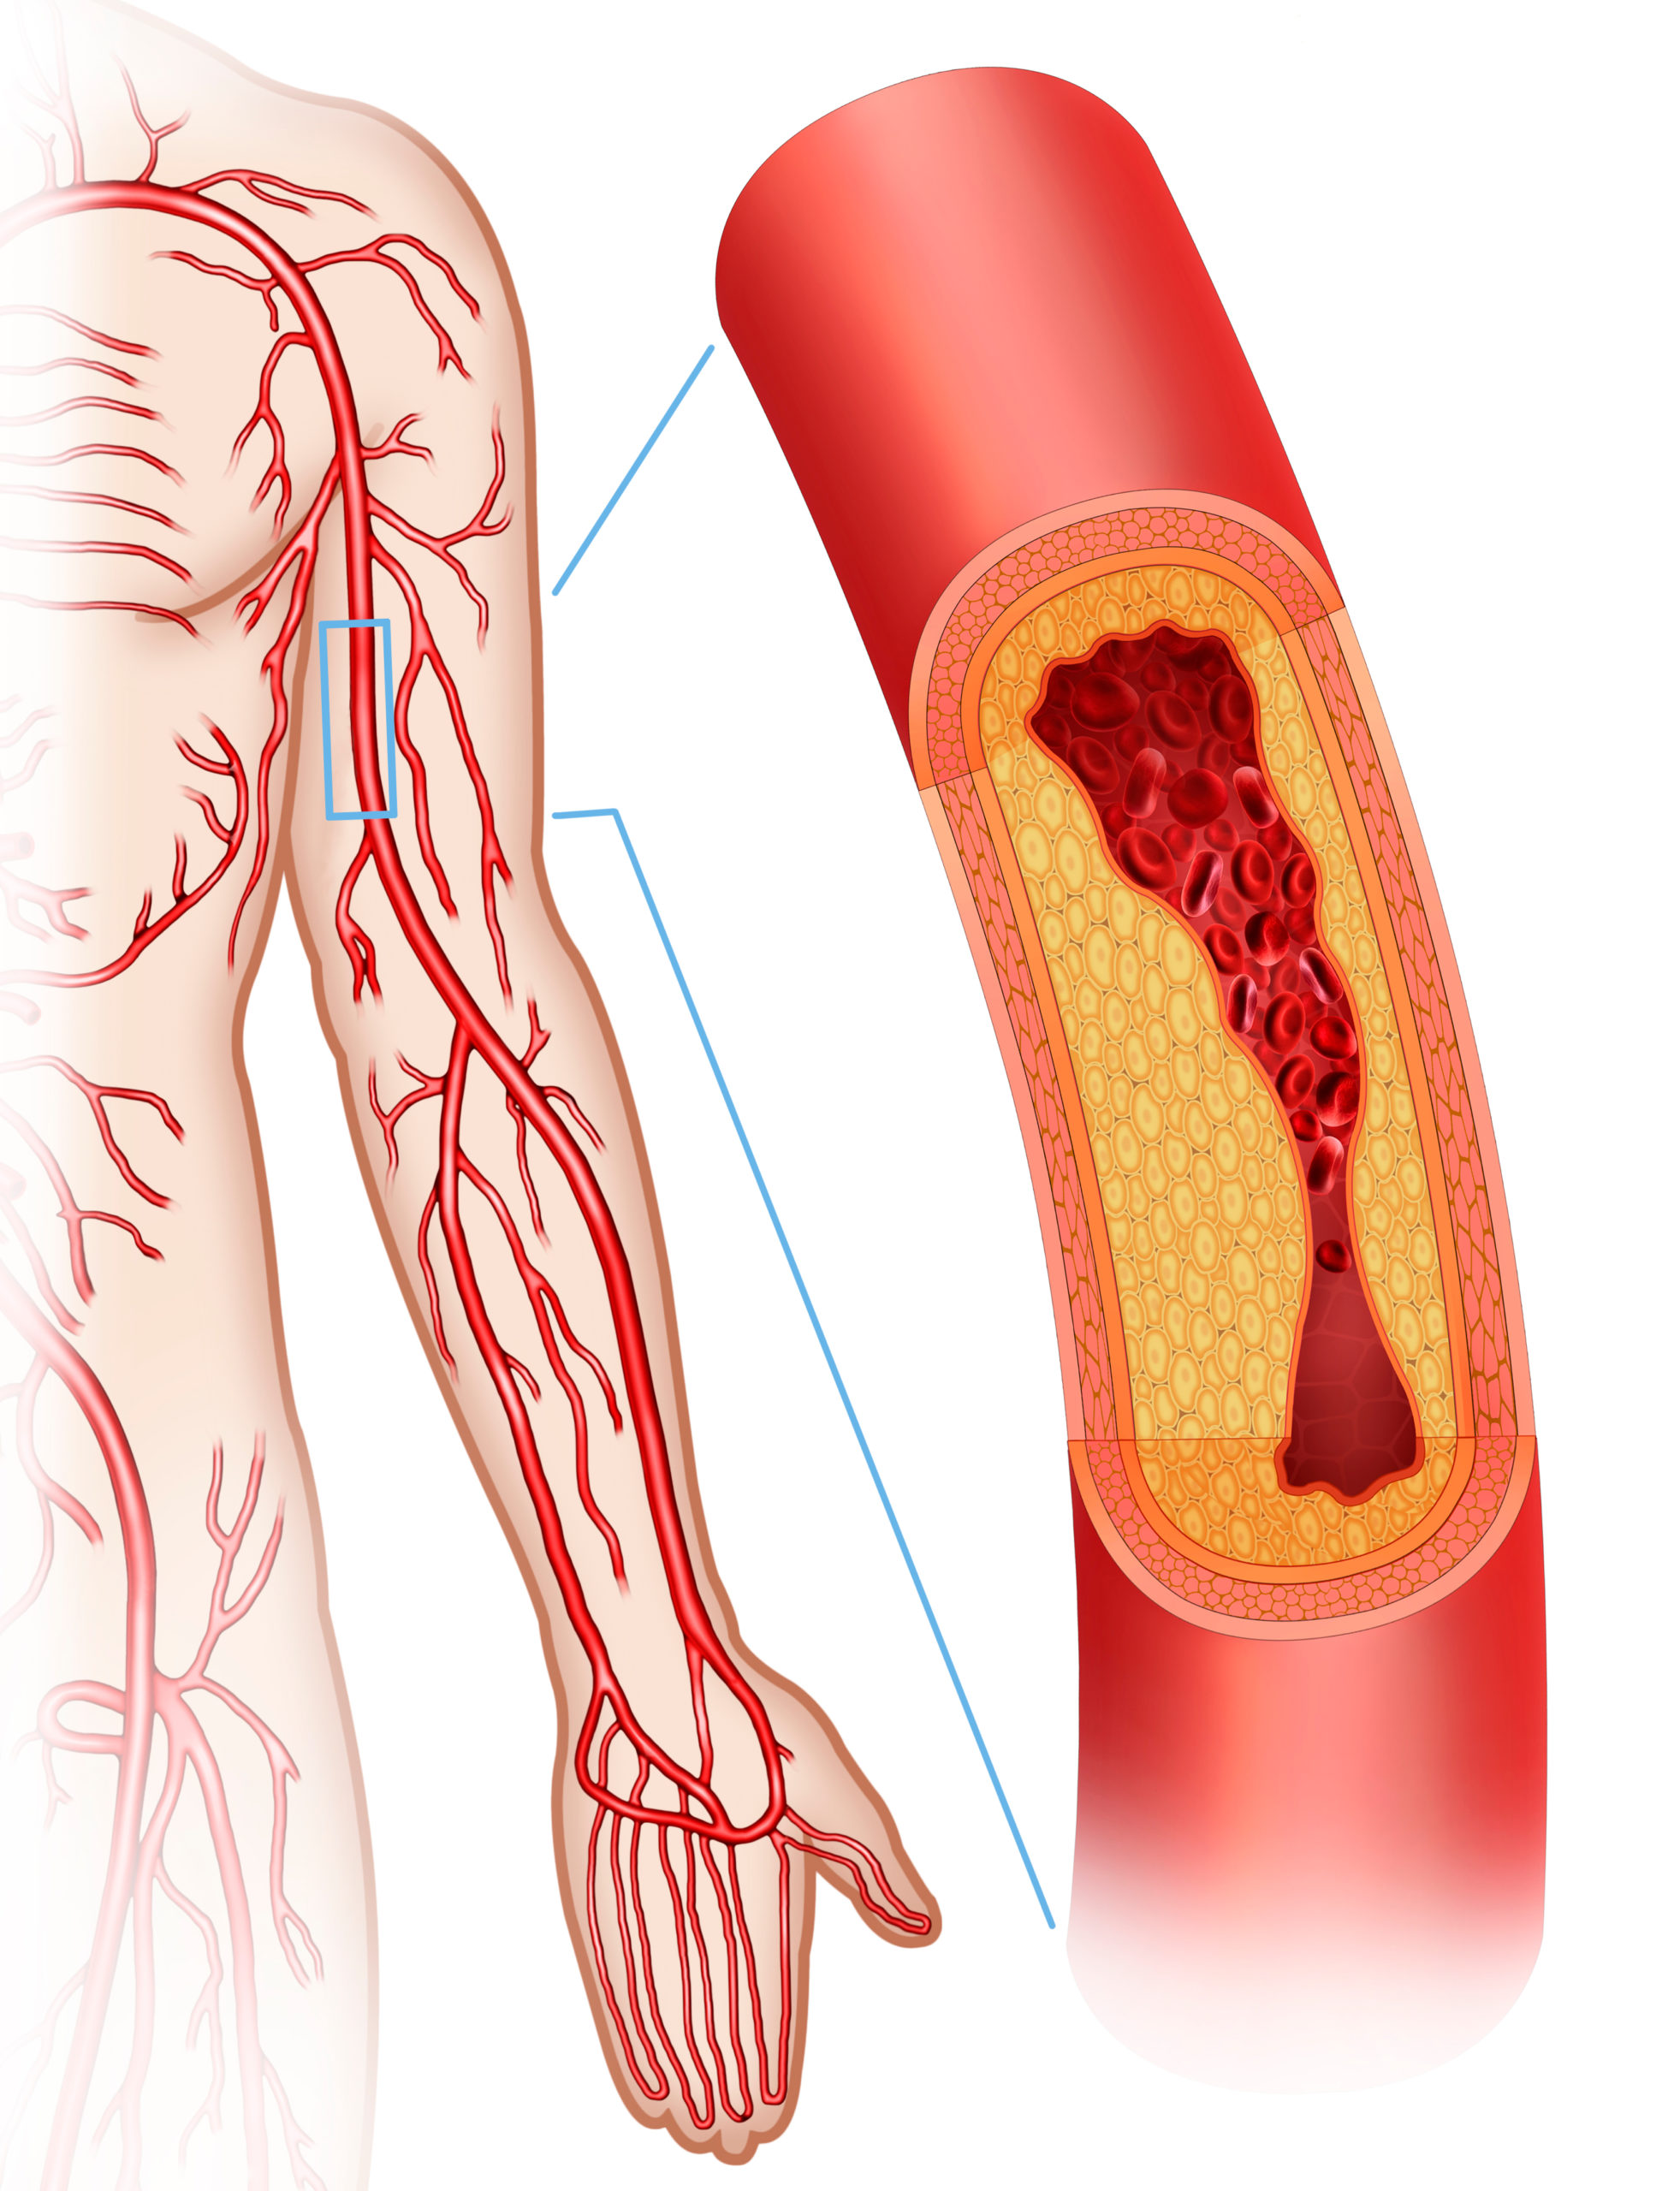

peripheral artery disease

Peripheral artery disease (PAD) is a significant contributor in cardiovascular morbidity and mortality; However, ...

The left subclavian artery (LSA) is an alternative access path for patients with severe peripheral artery disease (PAD), ...